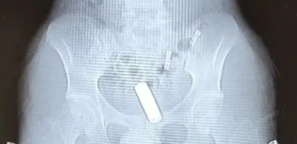

21岁的大学男生“小包”,将一节5号电池用纸巾包裹后,塞入了自己的“菊部”。可无法取出,狂喝水一天后也没排出,于是就到了杭州市中医院就诊。

由于已经过去了一天,拍片后发现,电池已经卡在了第一个肠袢。

其实类似的新闻之前报道了不少,就在相关搜索里,唐唐看到近日温州也有一例。还是13厘米的钢管!